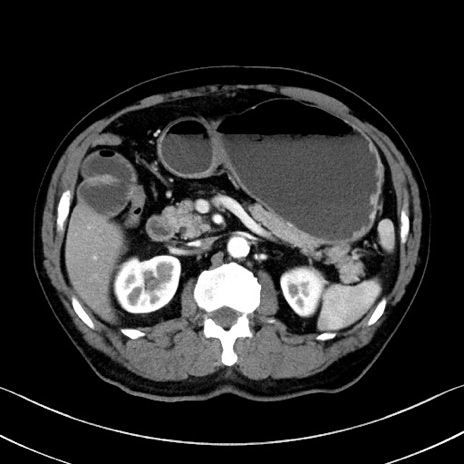

症例35(横断像)

【症例】70歳代 男性

【主訴】腹部膨満、嘔吐

【現病歴】昨日より腹部膨満感出現。本日増悪し、仙痛出現。嘔吐あり、受診。

【既往歴】糖尿病、胆摘後

【身体所見】BP 149/80mmHg、HR 74/min、BT 35.9℃、腹部:膨満、軟、圧痛なし。腸雑音減弱あり。上腹部正中切開瘢痕あり。

【データ】WBC 13500、CRP 1.72